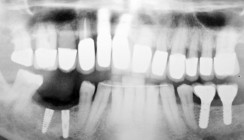

Foto: Dentegris

Die Dentegris GmbH mit Sitz in Duisburg ist spezialisiert auf Biomaterialien, Implantate und Implantatprothetik und bietet seit Neuestem die innovative Implantatplattform 3.8/4.1. Das aktuelle Portfolio und zukünftige Pläne erläutern Herr Matthias Matthes, Geschäftsführer von Dentegris, sowie Herr Detlef Hille, neuer Außendienstmitarbeiter NRW, im Gespräch.